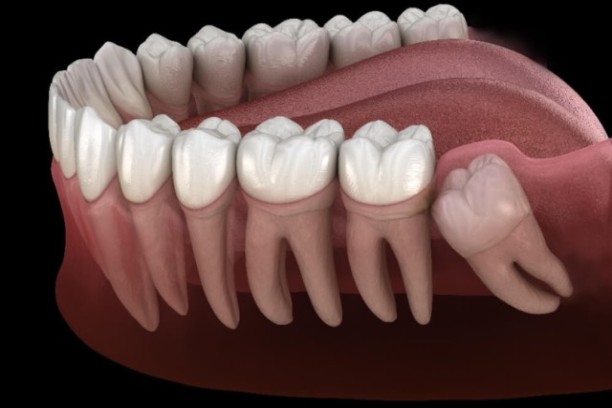

Impaction / Wisdom Tooth Removal

Safe and painless removal of impacted wisdom teeth to prevent pain and infection.